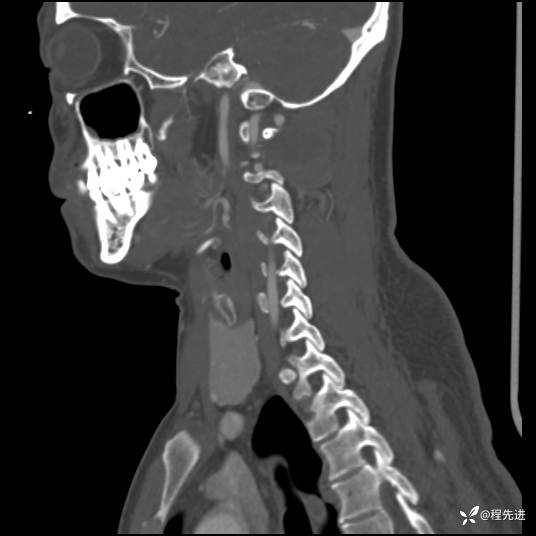

CT平扫+增强:

现病史:患者3个月前低头工作后感颈部疼痛,隐痛,活动颈部后稍好转,无上肢麻木不适,无肢体活动障碍,无头晕头痛,3个月来疼痛反复发作

患者性别:男

患者年龄:43岁

主诉:颈部疼痛3个月